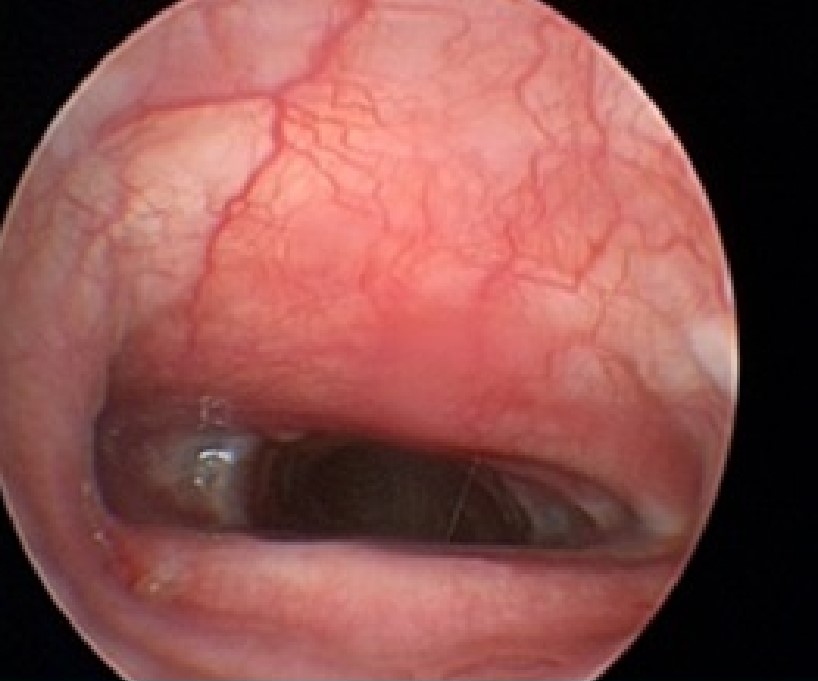

Thoracic radiographs were obtained in Kiley to rule out the presence of preexisting pneumonia and a full bronchoscopy was performed prior to fluoroscopy to grade and assess the degree and type of collapse. There is emerging evidence that the Grade IV collapse may be a different version of the disease and stenting may not be the best approach in these patients. Also, if bronchial collapse is present this may impact the outcome. Bronchial collapse by itself is not a reason to avoid stenting the trachea, but bronchial stents are not well tolerated or effective. Additionally, a wash was performed at the time of stent placement. In one study, endotracheal washes in dogs at the time of stent placement showed that 83% had evidence of inflammation, but surprisingly, 55% of dogs had positive airway cultures, indicating that the normal airway defense mechanisms are impaired in dogs with collapse. Kiley was diagnosed with Grade III intrathoracic tracheal collapse. Under fluoroscopic guidance a tracheal stent was placed spanning the length of the collapse and Kiley was recovered smoothly.